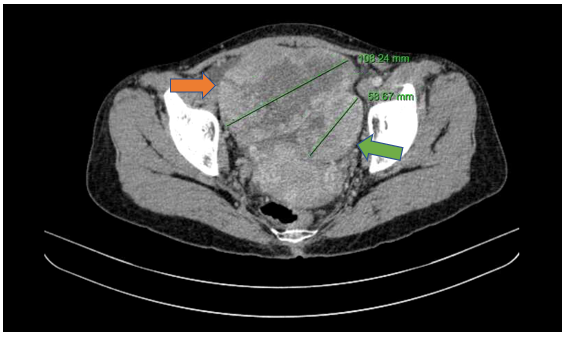

- Cắt lớp vi tính ổ bụng (30/06/2025): Cấu trúc dạng nang hỗn hợp tiểu khung nghi nguồn gốc từ buồng trứng hai bên.

Hình 5

. Hình ảnh khối buồng trứng phải kích thước ~108mm (mũi tên màu cam), khối buồng trứng trái kích thước ~58mm (mũi tên màu xanh lục) trên phim chụp cắt lớp vi tính.